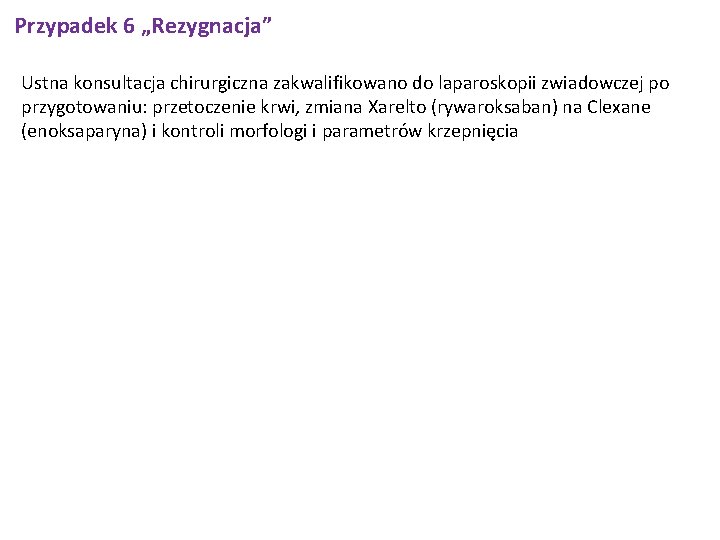

Przypadek 6 „Rezygnacja” Ustna konsultacja chirurgiczna zakwalifikowano do laparoskopii zwiadowczej po przygotowaniu: przetoczenie krwi, zmiana Xarelto (rywaroksaban) na Clexane (enoksaparyna) i kontroli morfologi i parametrów krzepnięcia

Przypadek 6 „Rezygnacja” Podejrzenie guza głowy trzustki. Niedokrwistość normocytarna. Przetrwałe migotanie przedsionków stan po skutecznej kardiowersji elektryczną (01. 12. 17 r). Przewlekła choroba wieńcowa. Stan po OZW-UA leczonym zachowawczo (2009). Stan po OZW-UA leczonym angioplastyką I Mg z implantacją stentu DES Orsiro (16/08/2016). Stan po CABG (LITA->LAD, SBG->IIMg, SBG->RCA) (22. 02. 2017). Przewlekła niewydolność serca z łagodnie upośledzoną funkcją skurczową lewej komory w II okresie hemodynamicznym wg NYHA. Łagodna niedomykalność mitralna i trójdzielna. Nadciśnienie tętnicze II stopnia wg ESH/ESC. Hipercholesterolemia. Zwężenie lewej tętnicy szyjnej. Cukrzyca typu 2 (na insulinoterapii). Kamica nerki prawej. Torbiel nerki lewej. Stan po TIA (2015). Choroba zwyrodnieniowa kręgosłupa. Stan po endoprotezoplastyce prawego stawu biodrowego. Stan po appendektomii. Rzekomobłoniaste zapalenie jelita grubego w wywiadzie (04. 2017). Nikotynizm w wywiadzie. Nadwaga.